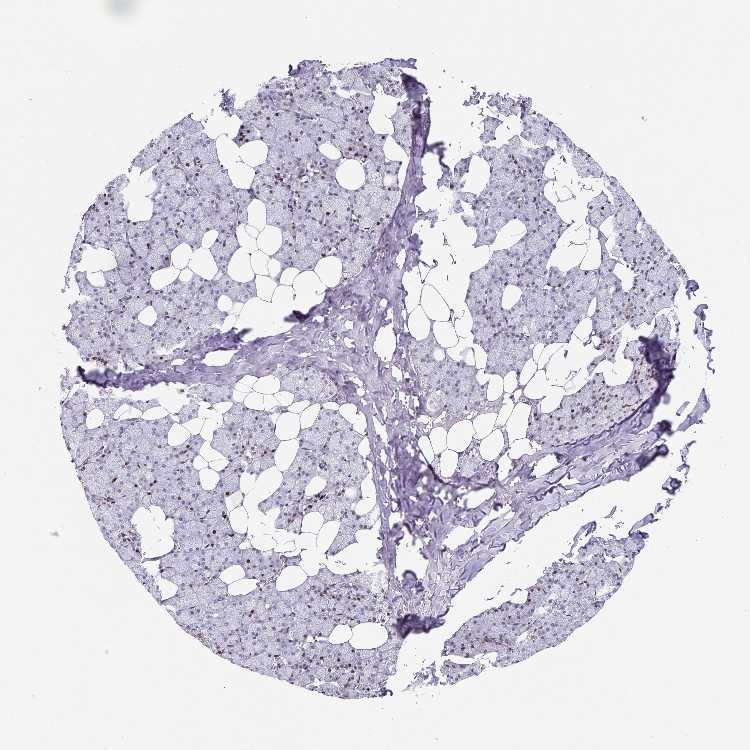

TISSUE PRIMARY DATA SALIVARY GLAND Show tissue menu

SALIVARY GLAND - Antibody stainingi

Antibody staining in the annotated cell types in the current human tissue is reported as not detected, low, medium, or high, based on conventional immunohistochemistry profiling in selected tissues. This score is based on the combination of the staining intensity and fraction of stained cells.

Each image is clickable and will lead to virtual microscopy that enables deeper exploration of all samples and also displays staining intensity scores, fraction scores and subcellular localization as well as patient and tissue information for each sample.

Antibody HPA049808Antibody HPA062476Antibody CAB018351

Glandular cells MediumNot detectedNot detected